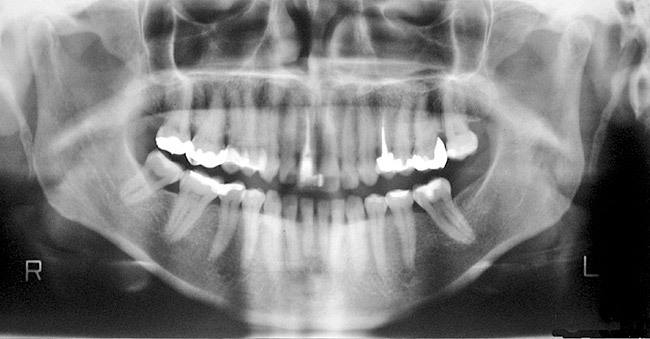

In addition to linear accuracy, it has been suggested that CBCT can have diagnostic accuracy with regards to periapical lesions.17-19 In one of these studies,17 periapical lesions were analyzed with CBCT, then surgically excised and biopsied to compare with histology. The authors found comparable results. Although the study showed promising results with CBCT, the researchers conceded that histology remains the gold standard in the diagnostic armamentarium. In another study,19 the ability to identify periapical lesions was assessed using radiographs and spiral CT. With CT, 100% of lesions were identified, while only 78% were identified with radiographs alone. Concomitantly, the location of the lesions proximal to the inferior alveolar nerve was visualized more readily with CT (100% vs 39%). Figure 1A through Figure 1E illustrate a case in which an endodontically treated tooth appeared normal on panoramic and periapical radiographs. Only CBCT showed the presence of apical pathology.6

Figure 1a  Panoramic (A) and periapical radiographs (B, C) reveal the absence of periapical rarefaction in the area of the upper right central incisor. However, evidence of apical periodontitis can be seen clearly using the CBCT21 (D, E).

Figure 1a

Figure 1b  Panoramic (A) and periapical radiographs (B, C) reveal the absence of periapical rarefaction in the area of the upper right central incisor. However, evidence of apical periodontitis can be seen clearly using the CBCT21 (D, E).

Figure 1b

Figure 1c  Panoramic (A) and periapical radiographs (B, C) reveal the absence of periapical rarefaction in the area of the upper right central incisor. However, evidence of apical periodontitis can be seen clearly using the CBCT21 (D, E).

Figure 1c